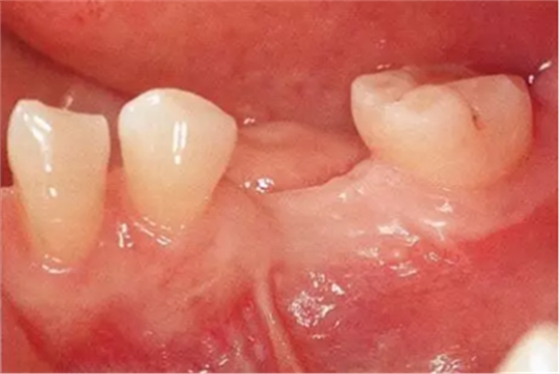

Type3-Class1

的病例(病例7):植入種植體前,牙槽嵴幾乎沒有角化齦,在植入前進行FGG獲得角化齦的病例

▲圖9-1

頰側(cè)和牙槽嵴幾乎沒有角化齦(Type3-Class1)

▲圖9-2,3

圖9-2 全損牙槽嵴的頂部,將牙齦移植片固定在頰側(cè)方向。待牙齦愈合后植入種植體。

圖9-3 牙齦愈合后的狀態(tài)。缺損牙槽嵴和頰側(cè)均獲得了角化齦。

▲圖9-4

佩戴最終修復(fù)體時的狀態(tài)。